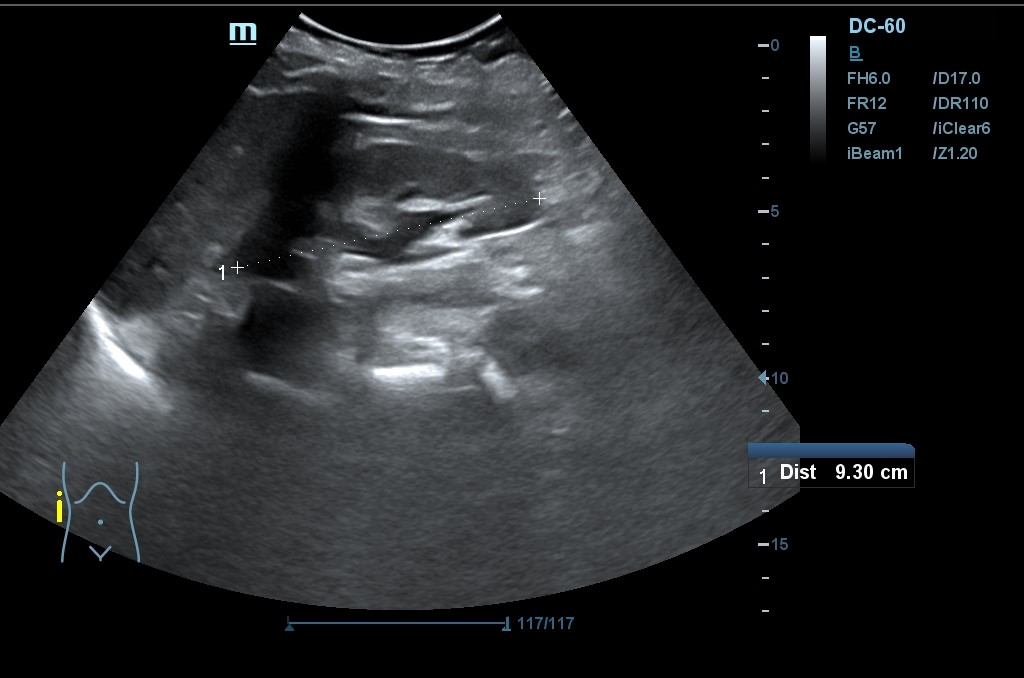

Hallazgo de lo que impresiona de nefromegalia izquierda de aproximadamente 14 cm con hidronefrosis bilateral grado 2.

Tras la segunda ecografía se deriva a la paciente a la Unidad de Diagnóstico Rápido de Medicina Interna donde ingresa para completar estudio. Tras ecografía en la que informan de extenso tejido hipoecoico periaórtico y perirrenal izq. (nefromegalia izq.) con extensión nodular al mesenterio, se establece la sospecha de síndrome linfoproliferativo, así como en un TC posterior y que se confirma como Linfoma No Hodgkin mediante biopsia.